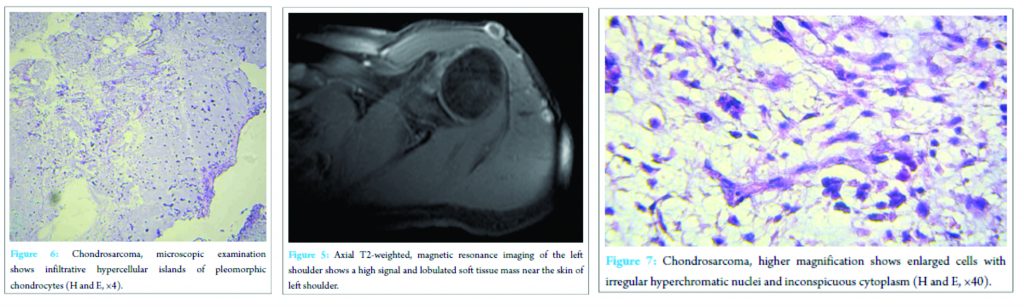

First, we decided to operate the tumor as an incisional biopsy because we were not sure about the nature of the lesion. An important note in this approach was limited access to the lesion because of an incorrect previous approach. Pathologic specimen confirmed the diagnosis of chondrosarcoma. Then, he underwent a wide resection of the lesion in the beach-chair position. In surgery, the five dense fibrotic and firm masses measuring from 0.5 to 2 cm and the middle part of deltoid muscle (because of involvement) were excised and sent to pathology ward. Microscopic examination showed infiltrative hypercellular islands of pleomorphic chondrocytes composed of enlarged cells with irregular hyperchromatic nuclei and inconspicuous cytoplasm which was compatible with the diagnosis of chondrosarcoma with free surgical margins (Figs 6,7). We should say that the diagnosis was based on the characteristic clinical, radiologic and pathological criteria; moreover, it was confirmed by immunohistochemistry (IHC).Hence, after consulting with the oncologist, radiation therapy was done. We have followed the patient for 6 months after operation and until now no recurrence is recognized.